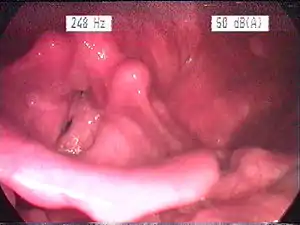

| Endoscopic image of an inflamed larynx caused by acid reflux | |

Visual diagnosis

The larynx itself will often show erythema (reddening) and edema (swelling). This can be seen with laryngoscopy or stroboscopy (method depends on the type of laryngitis).[7]: 108 Stroboscopy may be relatively normal or may reveal asymmetry, aperiodicity, and reduced mucosal wave patterns.[22]

Other features of the laryngeal tissues may include

- Redness of the laryngeal tissues (acute)

- Dilated blood vessels (acute)

- Thick, yet dry laryngal tissue (chronic)

- Stiff vocal folds

- Sticky secretions between the vocal folds and nearby structures (the interarytenoid region)